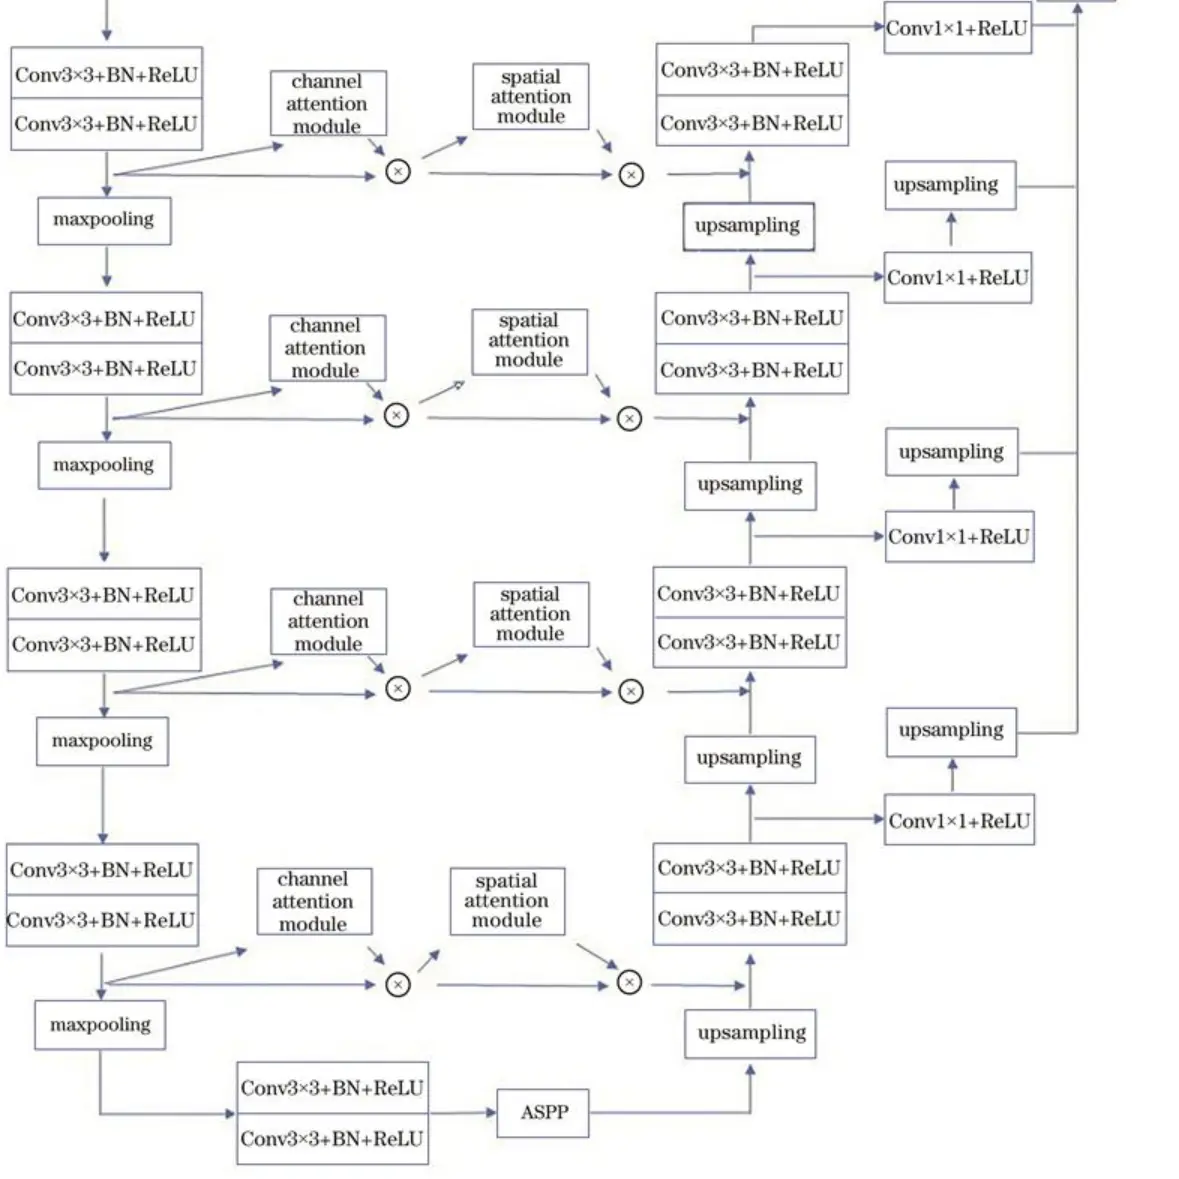

在RonnebergerO等人的工作中针对上述问题设计了独特的特征提取结构:UNet模型,该模型被提出之后在后续的代码实现上有一些改进,略微不同于原论文的描述,但目前对UNet的具体实现一般如图所示,其中C表示对应特征图的通道个数,Conv表示卷积层,CBR表示卷积层、Batch Normalization操作以及ReLU激活函数的组合,Conv和CBR前面的3x3或者1×1均表示其中卷积层的卷积核大小。

总体来说,UNet模型主要包括U型的编解码结构以及中间的横向连接结构,这种结构包含了两种特征传递路径,第一个路径是将深层的特征逐层上采样,第二个路径是将浅层的特征逐层和上采样的深层特征进行融合,这种结构设计最终可以输出高分辨率的特征图,并且该特征图上的每个像素特征都包含高分辨率的低级语义信息以及低分辨率的高级语义信息,这种特征对于语义边界较为模糊的分割任务有较大的帮助,另外相对于其他分割模型,UNet模型的结构简单,参数量较少,且由于横向连接的存在,训练过程中不容易出现梯度消失的情况,收敛速度更快,因此对标注数据数量的要求不高。在医学图像分割领域,一般存在语义边界较为模糊、标注数据量较少两个问题,UNet对于这两种问题都有较好的缓解,因此UNet 结构成为了目前深度学习医学图像分割领域的最常见模型结构。

8.改进的MA-Unet结构

参考该博客给出的改进方案,MA-Unet分为两个部分,分别为编码器与解码器。由于U-Net在跳跃连接时存在无效的语义信息,故在编码器中每一层的特征图在经过卷积层之后加入CBAM。在CBAM的通道注意力模块中,通过通道注意力机制来加强特征,抑制其他无效特征,从而提高网络精度;在CBAM的空间注意力模块中,空间注意力机制可从已进行上采样的特征图中恢复空间信息。针对U-Net对尺度信息提取不足的问题,在编码器最后一层通道数为1024的特征图后加入改进的ASPP模块。通过ASPP模块可以实现对不同尺度特征的提取,在低层阶段获得精细的目标像素分割定位,在高层阶段提取更为有效的特征,从而提高分割精度。在解码器中,为了解决图像存在的不同尺寸的物体的多尺度问题,对每一个尺度的特征图进行串联,在最后进行提取时,特征图包含了各个尺度的信息特征。通过跨尺度信息聚合的方式可以解决“同物异谱,异物同谱”的问题。

9.空洞空间金字塔池化模块

在CT图像中,在进行语义分割的过程中小型对象易被忽略,这种空间信息的损失通常是在网络模型中持续的池化操作导致的。在进行池化时,固定的池化核会让提取到的特征具有一定的局限性。通过提取不同尺度的特征,可以提升对小型病灶的提取效果。针对以上问题,引入ASPP模块[14]来进行病灶提取。

其中也在该模块中使用空洞卷积,它可以在不增加网络参数量以及不降低特征维度的情况下增大感受野,从而提升分割效果。针对CT图像中存在的不同尺度物体的分割精度问题,本文将改进的ASPP模块加入到网络中。ASPP模块内经过改进的空洞卷积的空洞率为3、5、7,特征图经不同空洞率的卷积层处理后再进行上采样操作,之后堆叠为特征金字塔,然后对输出结果进行融合。改进的ASPP模块通过不同空洞率的并行滤波器提取到了不同尺度的特征,解决了CT图像分割中病灶大小各不相同的问题。

10.卷积块注意力模块

卷积块注意力模块结合了通道注意力机制与空间注意力机制,相较于只关注通道域的SE模块,CBAM在通道域和空间域两个维度推算注意力图,可筛选出更重要的语义特征,因此可以取得更好的效果,具体结构如图所示。

首先将特征图输入到通道注意力模块中得到对应通道的权重,得到加权结果后将加权后的特征图输入空间注意力模块中得到对应权重,加权后输出特征图,计算方法表示为: